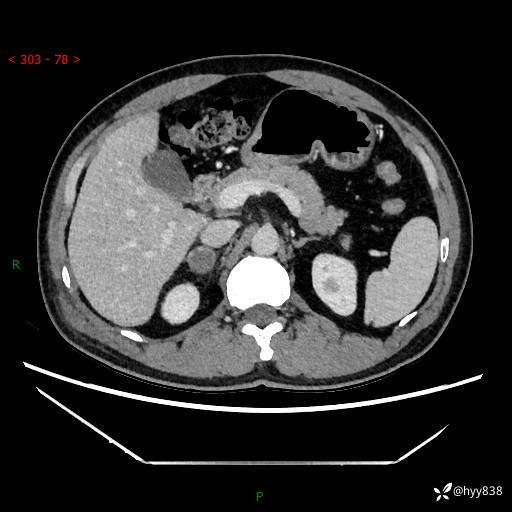

现病史:患者9月4日摔伤在深圳市宝安区中心医院行CT检查提示右侧肾上腺区结节(38*27mm),复查B超提示右侧肾上腺区可见一61*24mm异常低回声团,建议进一步检查。进一步完善增强CT后提示:右侧肾上腺区肿块及周围渗出改变,大致同前,考虑肾上腺腺瘤,不除外瘤内出血可能,否认阵发性头晕、头痛、出汗、乏力等不适,门诊以“ 右侧肾上腺肿瘤”收入住院。 起病来,患者精神、食欲、睡眠可,大便通畅,小便如上述,体力体重无明显改变。

肾上腺CT平扫

增强(动脉期+静脉期)